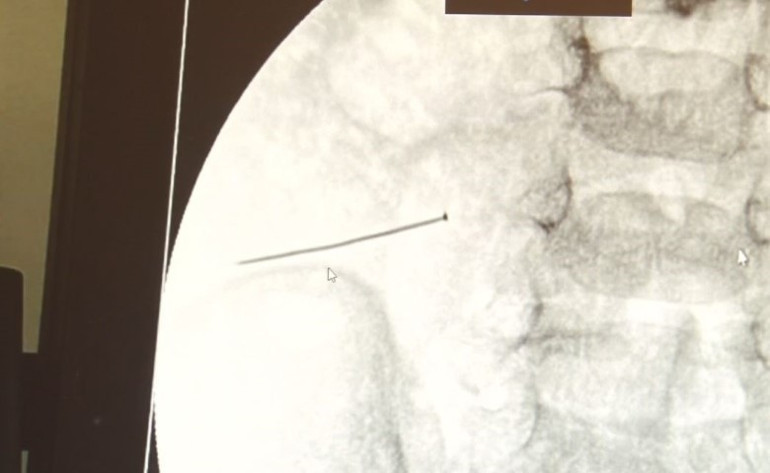

Ameliyat sonrası çekilen görüntülerde, 3 santimlik toplu iğnenin durumu dikkat çekti.

İstanbul'da yaşayan 2 yaşındaki bir çocuk, iddiaya göre bir toplu iğne yuttuktan sonra karın ağrısı nedeniyle yerinde duramaz hale geldi. Küçük çocuğun acı çektiğini fark eden babaannesi, onu Şehit Prof. Dr. İlhan Varank Sancaktepe Eğitim ve Araştırma Hastanesi'ne götürdü. Hastanede yapılan incelemelerde çocuğun ince bağırsağında yaklaşık 3 santim uzunluğunda bir toplu iğne tespit edildi ve bu iğnenin bağırsağı deldiği belirlendi. 30 Ekim akşamı Çocuk Cerrahisi Kliniği Eğitim ve İdari Sorumlusu Doç. Dr. Sefa Sağ ve ekibi hemen ameliyata alarak durumu kurtardı. Ameliyat yapılan çocuk, aileye büyük bir rahatlama getirdi. Doç. Dr. Sağ, taburcu edilen hastasıyla ilgili bilgi verirken yabancı cisim yutma riskine karşı aileleri uyardı.

Çocuklarda yabancı cisim yutma olgusunu açıklayan Doç. Dr. Sefa Sağ, “Soluk borusuna kaçması durumunda, çocuğun ölümü veya hayatı boyunca yatağa bağımlı kalması gibi ciddi sonuçlara neden olabiliyor. Yutulduğunda, gastrointestinal sistemin herhangi bir yerinde takılmadığı sürece çoğu yabancı cisim kendiliğinden dışarı çıkabilir. Ancak kesici ve delici aletlerin yutulması gastrointestinal sistemde delik açabilir. Bu çocuğumuzda da böyle bir olay yaşanmıştı. Ailenin bir gün önce toplu iğne yuttuğunu tahmin ettik ve ertesi gün bağırsakta delinmeye neden oldu. Tetkikler sonucunda yabancı cismi tespit ettik ve hemen ameliyat ettik. Toplu iğnenin ince bağırsağı deldiğini ve içeriğin karın içine dolduğunu gördük. Ameliyatı 1 saat içerisinde başarılı bir şekilde tamamladık” dedi.